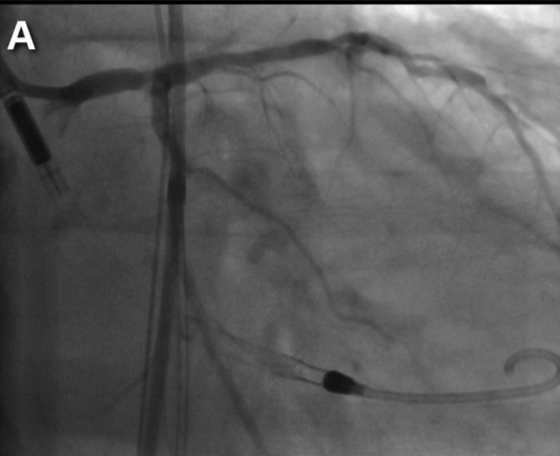

Protected PCI to left main and left anterior descending using ...

A step-by-step protected high-risk PCI with the Impella CP

Impella CP-protected PCI status post abdominal aortic aneurysm repair